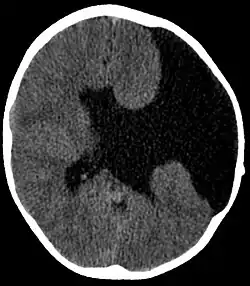

A esquizencefalia é uma rara malformação congênita que se caracteriza por fenda unilateral ou bilateral nos hemisférios cerebrais. Essa fenda normalmente se estende do córtex à região periventricular.

Pode pertencer ao tipo I, quando as duas corticais são justapostas (denominada esquizencefalia de lábios fechados) ou ao tipo II, quando a fenda é preenchida por líquido cefalorraquidiano (denominada esquizencefalia de lábios abertos).[1]

A tomografia computadorizada é capaz de detectar a anomalia, embora a ressonância magnética seja mais recomendada por proporcionar análise mais detalhada.[2]